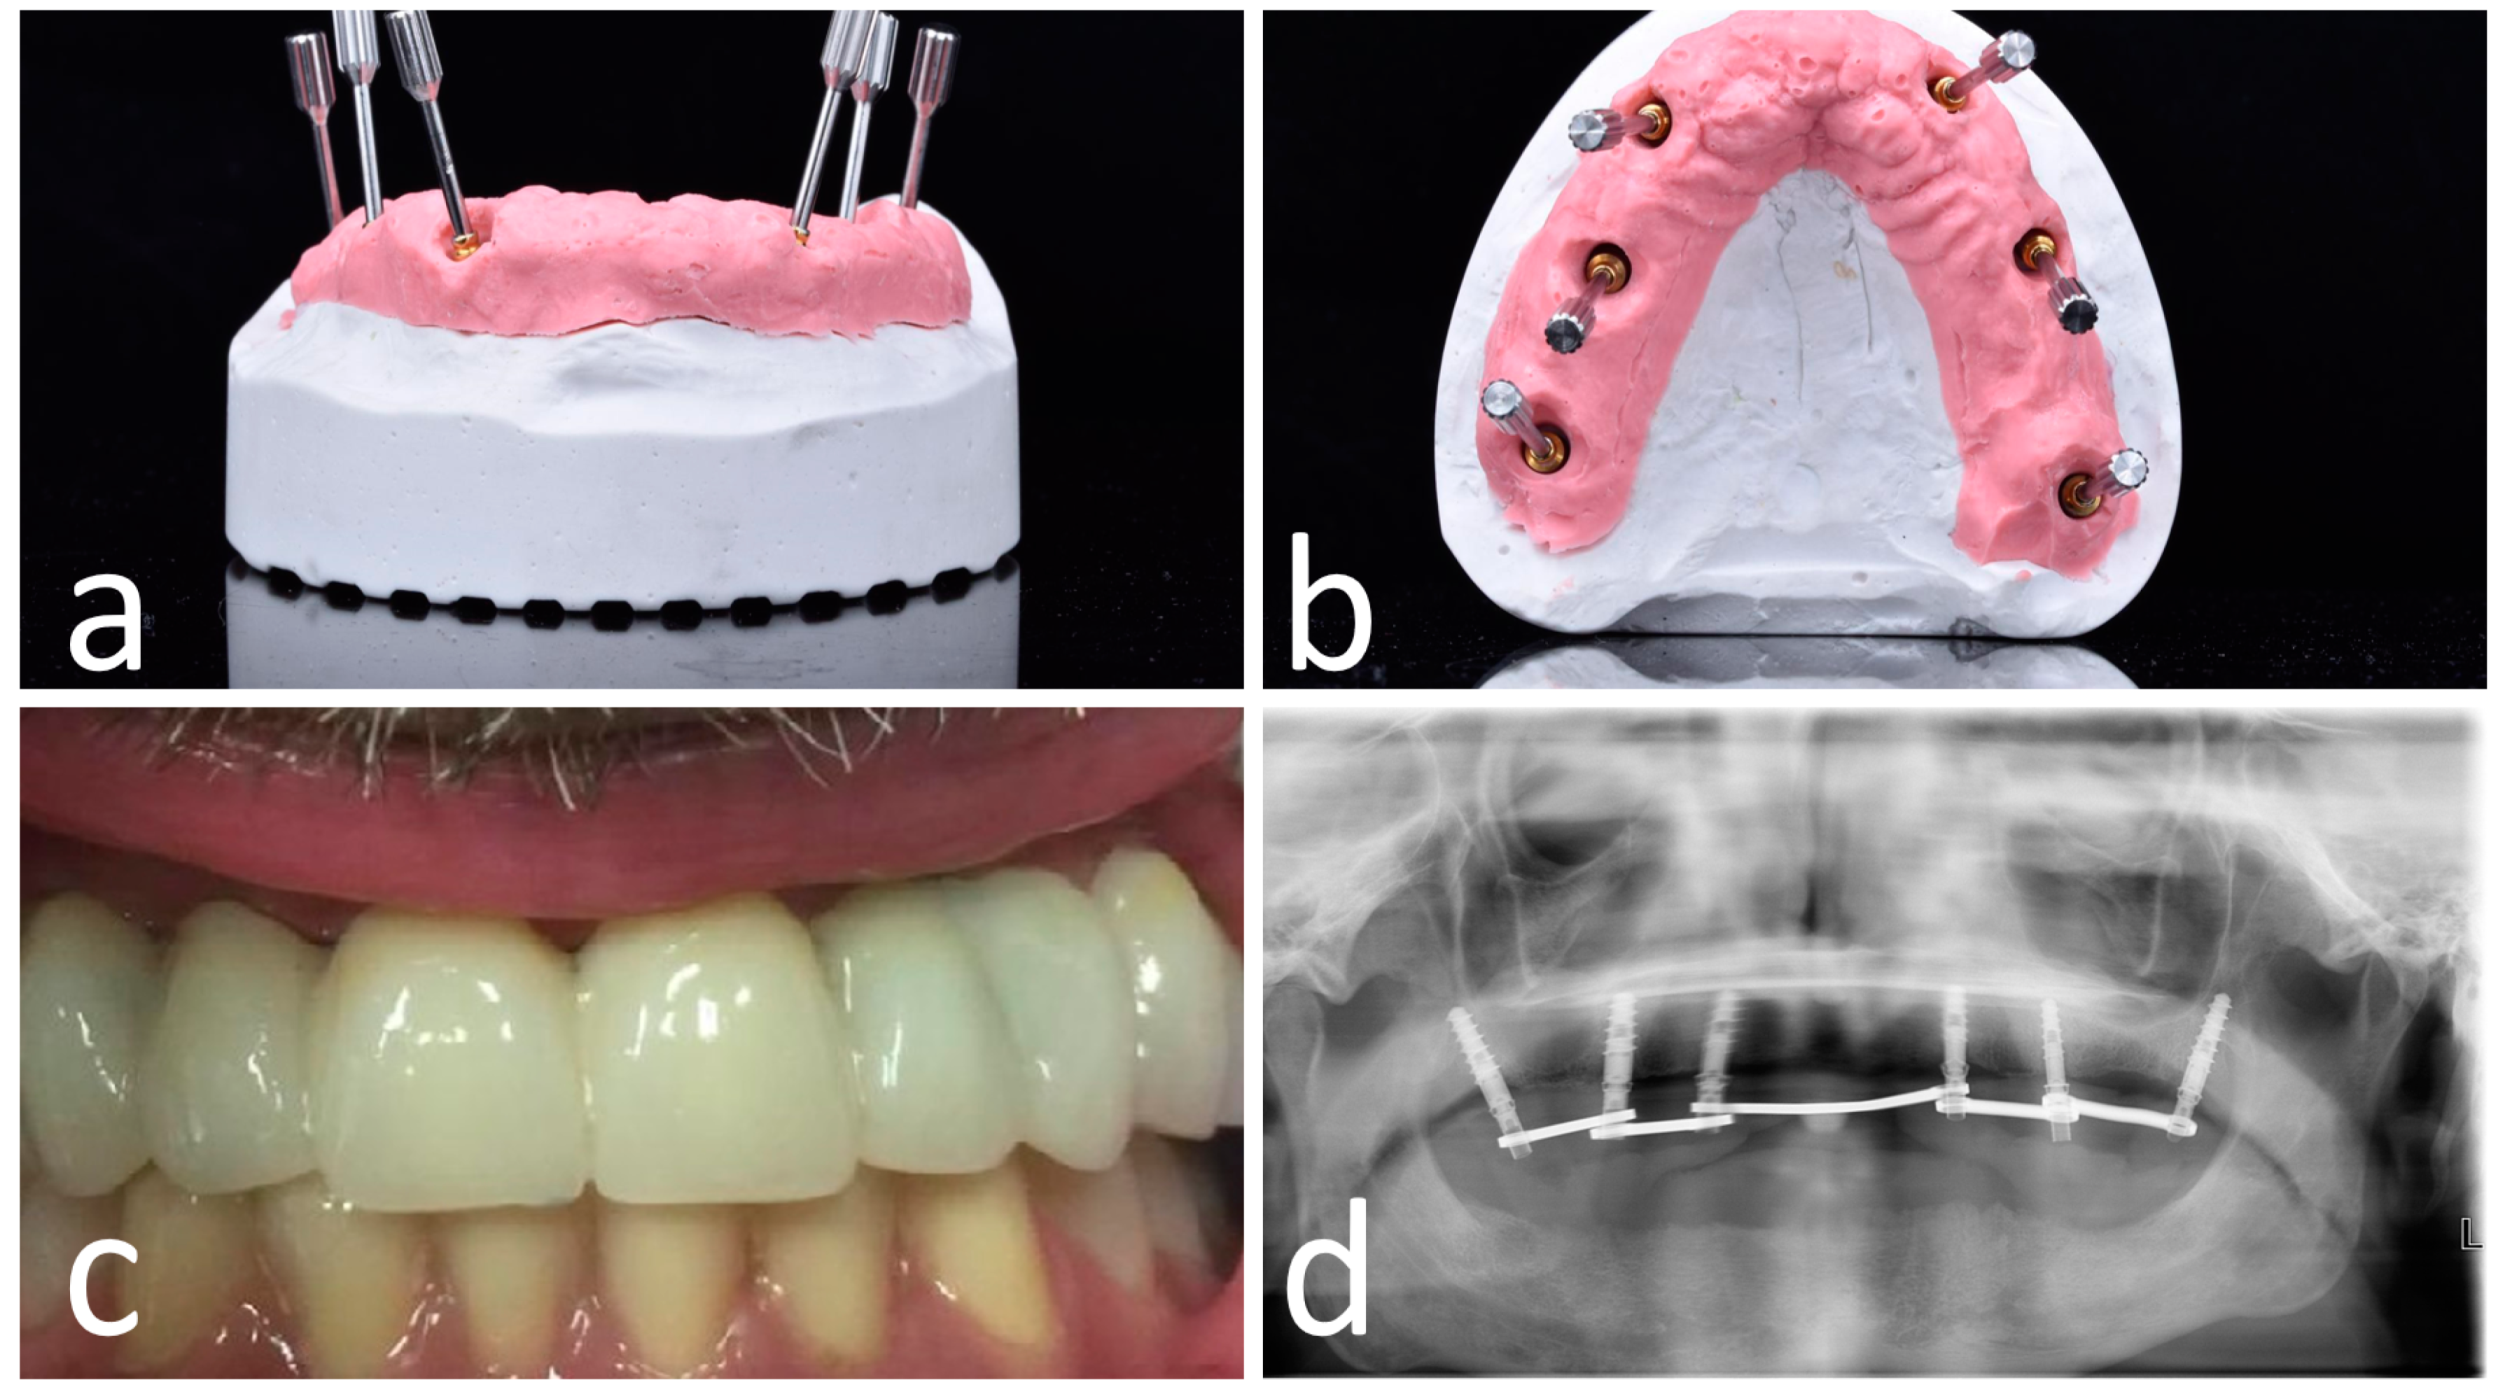

Figure 6.

OT-bridge abutments use the “Extragrade™” feature, a system allowing to compensate up to 80° of the divergence between two implants (a,b). Pictures c and d show the clinical (c) and X-ray (d) view of the provisional prosthesis using OT-bridge abutments.